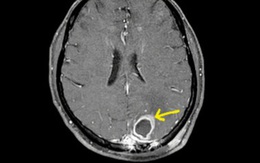

‘Vi khuẩn ăn thịt người’ tấn công não người bệnh

Thời gian qua, Bệnh viện Bạch Mai liên tục tiếp nhận nhiều bệnh nhân nhiễm vi khuẩn Whitmore (hay còn gọi là "vi khuẩn ăn thịt người"), trong đó có bệnh nhân phát hiện ổ áp xe trong não, mủ có chứa vi khuẩn Whitmore.